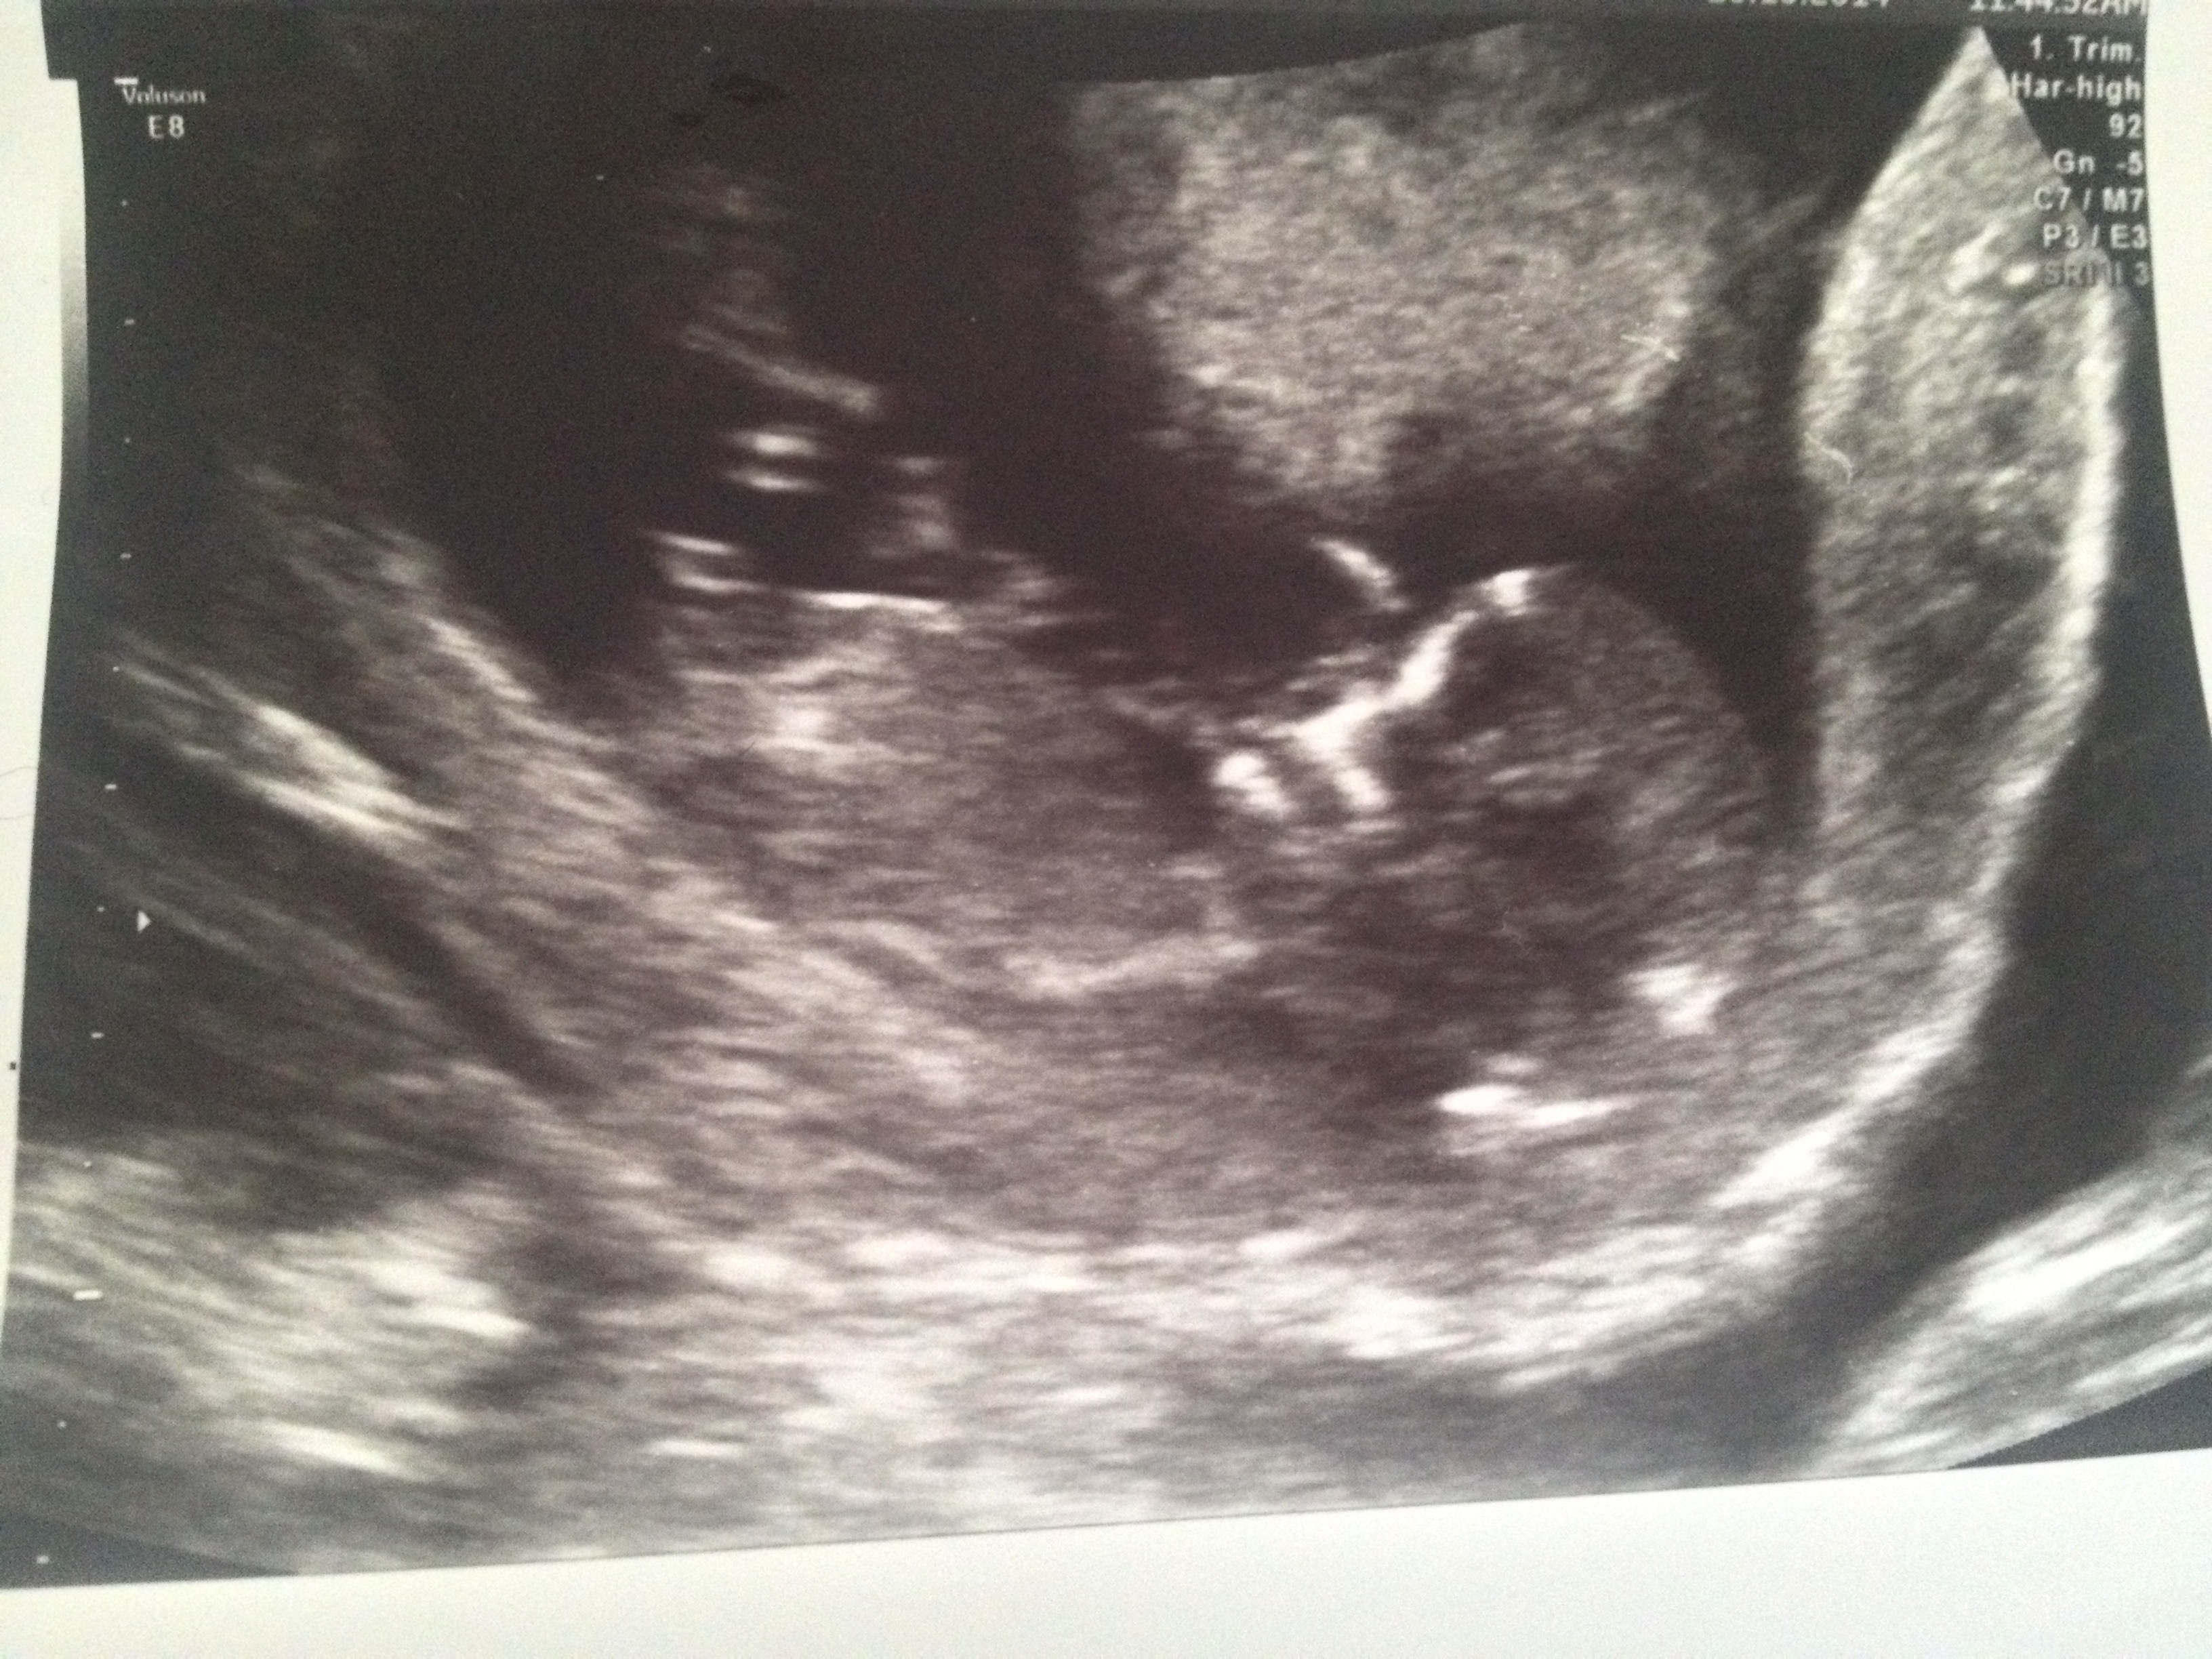

Attachment 22162Attachment 22163 Any guesses?

Boy, from pic 2:)

Thanks to everyone for their guesses so far. Anyone else?